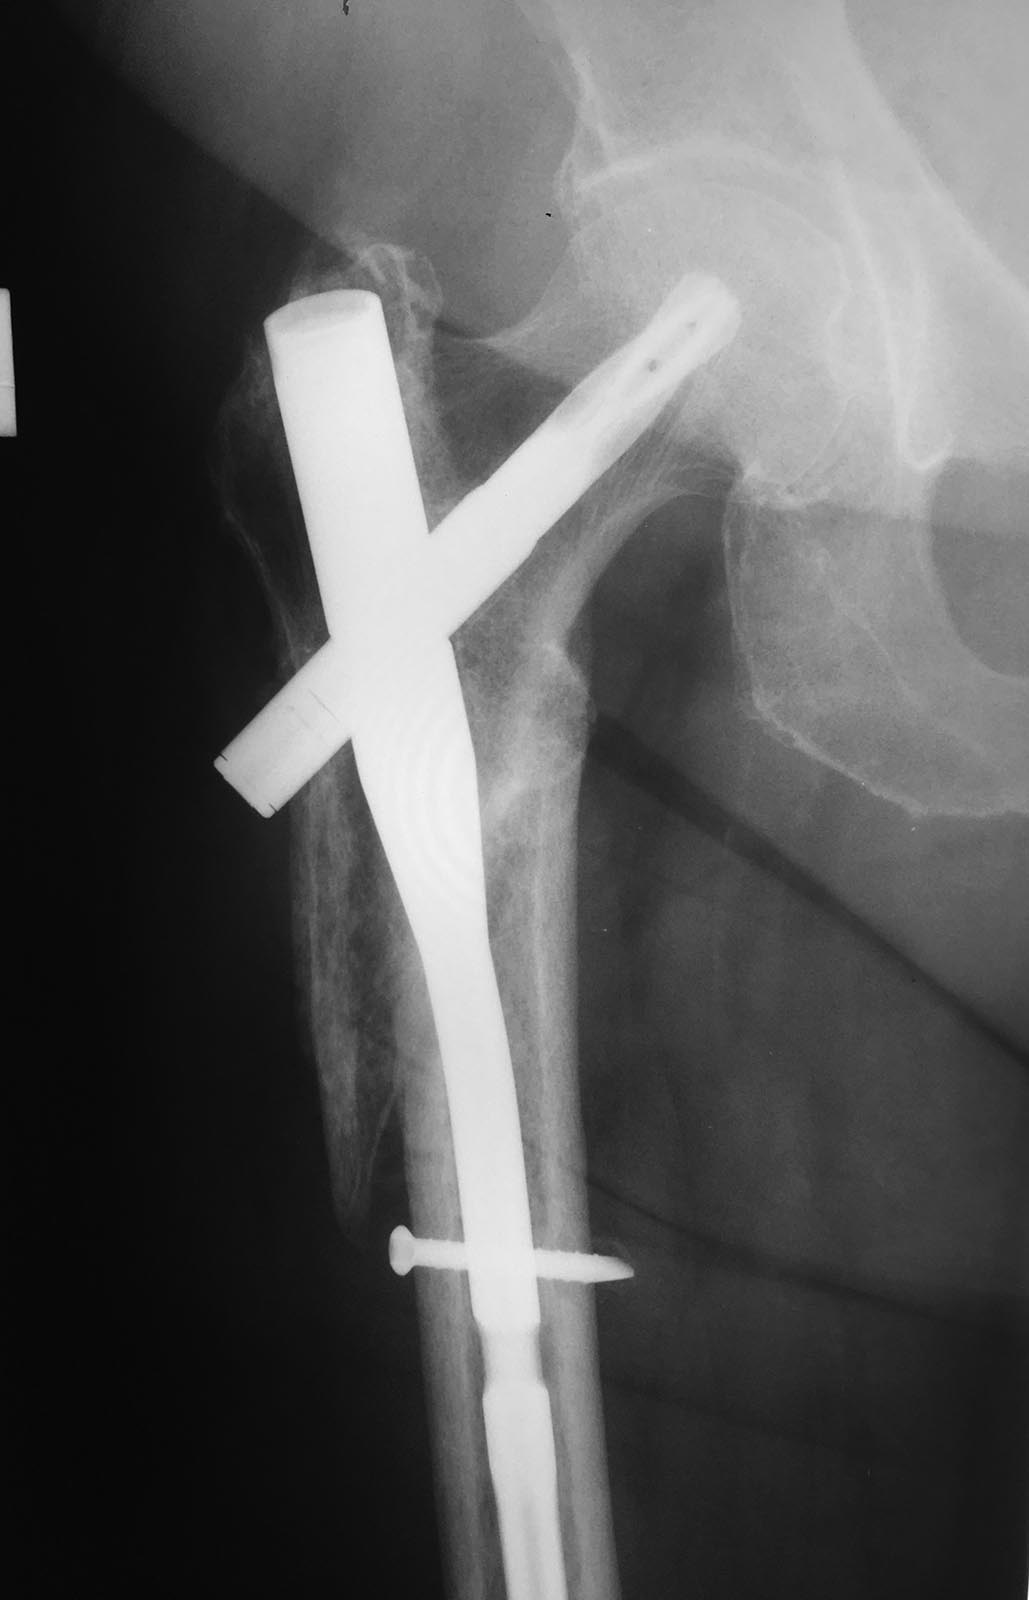

PFN

Ваше мнение о тактике ведения пациентки через 6 месяцев после остеосинтеза.

Пациентка 72 лет. 6 месяцев назад остеосинтез подвертельного перелома бедренной кости. Ходит с костылем. Впервые обратилась на прием 2 месяца назад. Передвигалась с 2 мя костылями, рекомендовал перейти на 1 костыль. На сегодняшний день опереться на ногу, оторвав здоровую от пола, не опираясь руками, не может. Аксиальный снимок, к сожалению, рентгенологи не могут выполнить (4 месяц как работаю в госполиклинике, воюю с рентгенолагами, обьяснял, бесполезно - аксиальных снимков не делают). Сейчас отправил на МСКТ. Хотелось бы услышать Вашего мнения. Обращаться туда где оперировалась не хочет/не может (это так, для исключения подобных рекомендаций).

Здравствуйте. Интересно, где находится дистальный винт, отверстие в стержне ниже винта. Если это PFNA Synthes, то в нем только одно отверстие для статической и динамической блокировки. Получается, что дистально не заблокировано, есть нестабильность, отсюда вялая консолидация (если она вообще есть)

Я думаю многие понимают вероятное смещение проксимального отломка в данном случае, также можно додумать положение клинка в шейке; наличие или отсутвия дистального блокирования, но это все предположения. Консультируя данную пациентку только по прямому снимку мы уподобаемся неквалифицированным рентгенологам, это не профессионально и с высокой вероятности приведёт к ошибке.